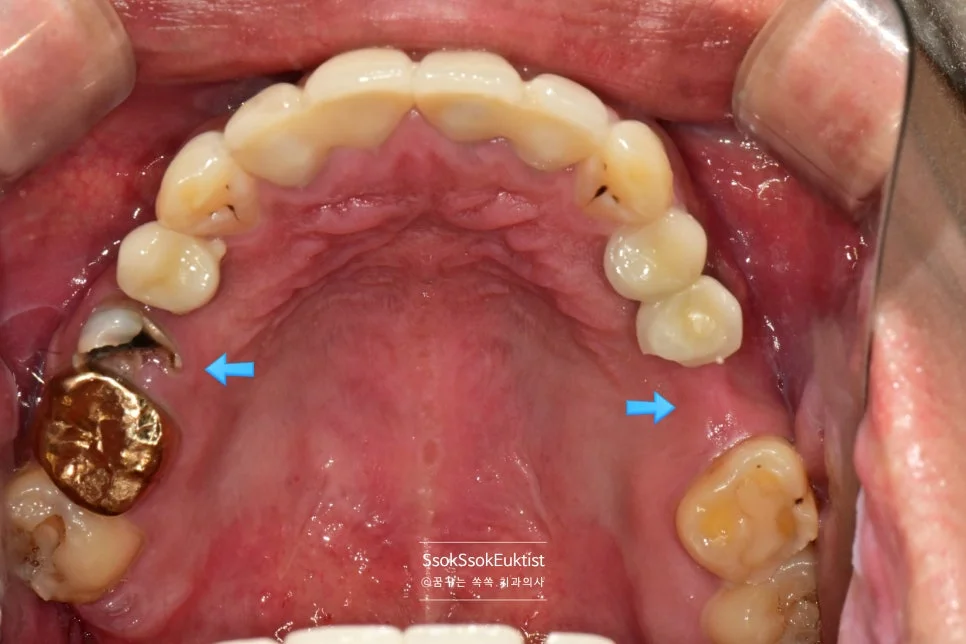

2차 수면 마취 — 우측 임플란트 3개 식립 완료 (화살표)

가능한 주변 골보다 2~3mm 깊게 임플란트가 온전히 뼈 안에 잠기게 식립되었다면 잘 심긴 임플란트입니다.

임플란트 식립한 자리 주변이 예쁘게 잇몸으로 아문 것을 볼 수 있습니다.

이제 묻혀 있는 임플란트를 꺼내어 보철물을 연결하면 치료는 마무리됩니다.

2번 자리의 잇몸을 보면 처음보다는 훨씬 건강한 잇몸이 된 것을 볼 수 있는데요. 한 달 후 체크 약속에서도

1개월 후 경과 관찰 — 2번 자리 잇몸이 건강하게 자리 잡아가는 모습

건강한 잇몸이 자리 잡아가는 것을 볼 수 있습니다.